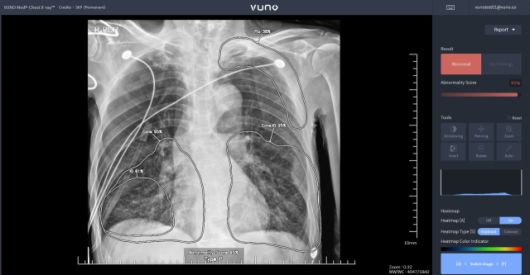

의료용 AI 진단보조 솔루션은 지난 2010년대 '딥러닝' 기술의 등장과 함께 가능성을 주목받기 시작했습니다. 초기 딥러닝 기술은 특히 이미지 속 특징 분석에 대단히 뛰어난 성능을 보였는데요. 당시 의료 AI 스타트업들은 이를 주로 환자의 엑스레이, CT/MRI 사진을 분석 프로세스에 접목하는 방식으로 의료진의 오진율 감소, 진단에 필요한 시간을 줄이는 데 도움을 주는 시도에 집중했습니다.

게다가 놀랍게도 2020년경, 이런 영상의학 계통의 AI 진단보조 솔루션들은 이미 평균 95% 이상의 정확도를 자랑했습니다. 이에 관련 제품군은 점차 뇌, 안구, 폐 등 주요 장기를 비롯해 질환별 특화 솔루션 등으로 세분화되었으며, 그에 따라 다수의 스타트업이 설립되며 초기 의료 AI 시장 형성에 큰 기여를 한 것으로 평가됩니다. 현재 미국 FDA 승인 의료 AI 기기의 약 70%도 영상의학 분야 AI 솔루션으로 알려져 있습니다.